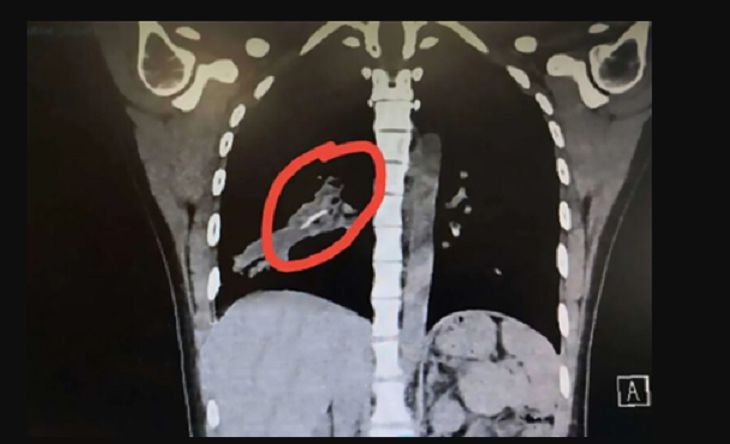

И на этот раз компьютерная томография определила инородное тело в правом легком.

На удаление инородного тела потребовалось более 30 минут, а сам объект в длину достигал более двух сантиметров.